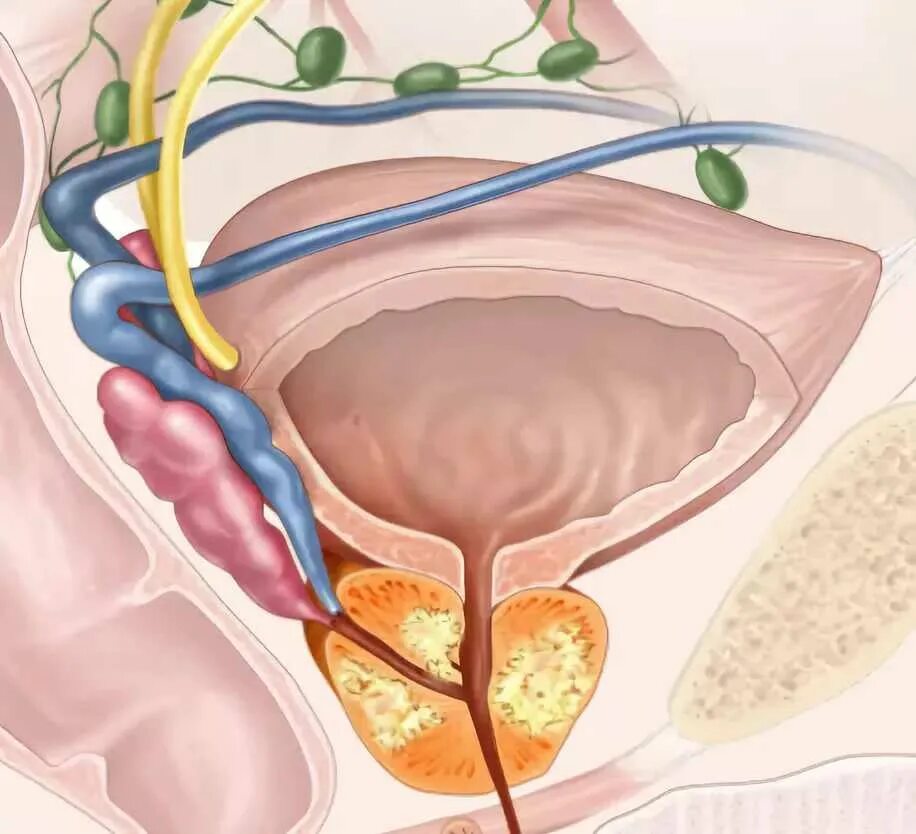

Предстательная железа MRT. Мультипараметрическое мрт предстательной железы. Предстательная железа кт норма. Аденома предстательной железы мрт Гистосканнинг предстательной железы. Трансректальная биопсия предстательной железы под контролем УЗИ. Ангиография предстательной железы. Лимфоузлы в предстательной железе

Гистосканнинг предстательной железы. Трансректальная биопсия предстательной железы под контролем УЗИ. Ангиография предстательной железы. Лимфоузлы в предстательной железе Фиброз предстательной железы. Объемное образование предстательной железы. Склероз в предстательной железе

Злокачественные новообразования простаты. Злокачественная опухоль предстательной железы в пожилом возрасте. Новообразования простаты злокачественной природы Сосудисто нервный пучок предстательной железы. Экстракапсулярная экстензия предстательной железы что это. Лучевая диагностика предстательной железы. Инвазия капсулы предстательной железы

Сосудисто нервный пучок предстательной железы. Экстракапсулярная экстензия предстательной железы что это. Лучевая диагностика предстательной железы. Инвазия капсулы предстательной железы Предстательная железа у мужчин. Представительна яжелеза. Опухальпредседательнойжелезы